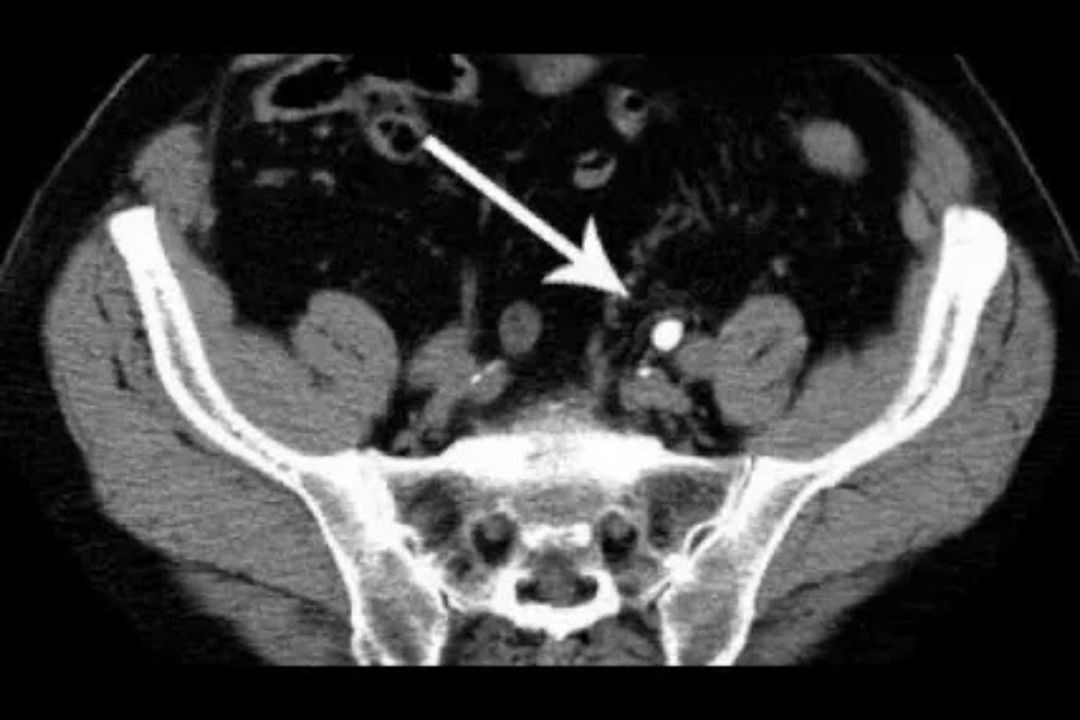

what is a ct kub plain scan? what conditions can a ct kub detect?

affordable ct scan for kidney stone diagnosis

ct scan for kidney stones diagnosis